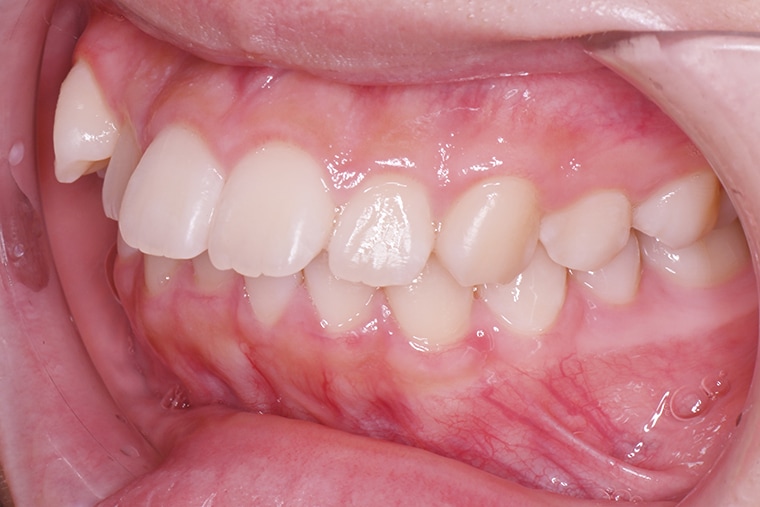

Case Study15歳女性出っ歯のマウスピース矯正-矯正期間10ヶ月

BEFORE

上の前歯が出っ歯で、笑ったときや話すときに口元が目立つのが気になり、娘も矯正をしたいと思っていました。